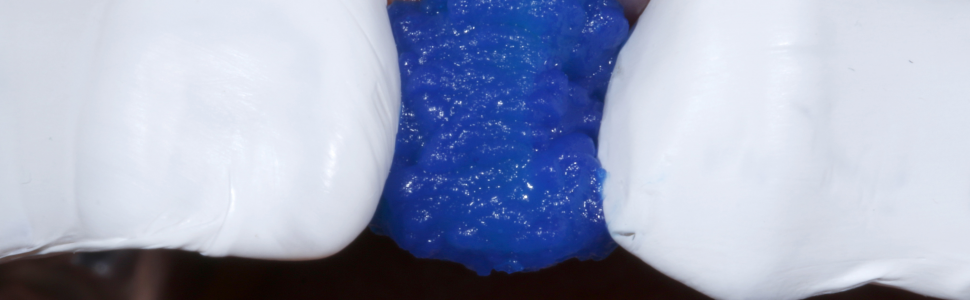

Następnie obszar osuszono sprężonym powietrzem. Miejscowe krwawienie w okolicy dziąseł zatamowano łatwo i skutecznie za pomocą pasty retrakcyjnej zawierającej chlorek glinu i kaolin (ryc. 8). Tylko czyste i suche pole zabiegowe pozwala na dalszą pracę bez zanieczyszczeń. W kolejnym etapie zabezpieczono oba sąsiednie zęby taśmą teflonową (ryc. 9).

Ryc. 9. Sąsiednie zęby zabezpieczono taśmą teflonową

Ryc. 10. Wytrawianie szkliwa i zębiny żelem zawierającym 35% kwas fosforowy.